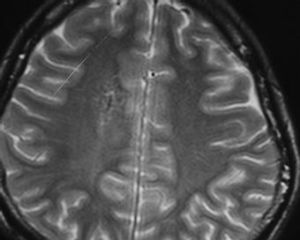

3.MRI掃描

其表現與CT所見相似。在T加權像上病灶為低信號,在T加權像上多為高信號,少數為低信號,注射對比劑後病灶呈現典型的放射樣星形或蜘蛛樣。